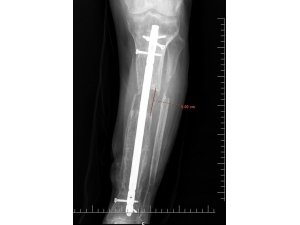

İsmi açıklanmayan bir erkek hasta, 5 yıl önce iş kazası geçirdi. Hastanın kaval kemiğinde parçalı kırıklar oluşması sonucu bacağı diğerine kıyasla kısaldı. 5 yıl boyunca aksayarak yürümek zorunda kalan hasta, Elbistan Devlet Hastanesi'ne başvurdu. Ortopedi servisinde Ortopedist Op. Dr. Ali Canbay ve Op. Dr. Serdar Karaman tarafından tetkikleri yapılan hastaya, boy (kemik) uzatma operasyonu yapılması kararlaştırıldı. Hastanın bacağına, ilk ameliyatında kısa olan kemiği günde 1 mm uzatma olacak şekilde bir sistem kuruldu. Başarılı geçen operasyon sonrasında kurulan sistem sayesinde 5 cm uzama ve yıllardır kaynamayan kemikte kaynama elde edildi. Son olarak dışarıdan uygulanan bu sistem çıkarıldı ve uzamanın kontrol altına alınması için çivi denilen işlem uygulandı. Hasta, tüm bu işlemlerin akabinde aksamadan yürümeye başlayarak eski sağlığına kavuştu.

Operasyonla ilgili Elbistan Devlet Hastanesi'nden yapılan açıklamada; "İş kazası nedeniyle beş yıl önce kaval kemiğinde parçalı kırığı olan ve kırık olan bacağında diğer bacağına kıyasla kısalığı devam eden hastamıza, Elbistan Devlet Hastanesi'nde Ortopedist Op. Dr. Ali Canbay ve Op. Dr. Serdar Karaman'ın birlikte yaptıkları iki operasyon sonucu hasta eski sağlığına kavuşmuştur. İlk ameliyatında kısa olan kemiği günde bir milimetre uzatma olacak şekilde kurulan sistem ile 5 cm uzama ve yıllardır bir türlü kaynamayan kemikte kaynama elde edilmiştir. Son olarak dışarıdan uygulanan sistem çıkarılıp hastanın konforlu hayatına dönmesi için çivi denilen işlem ile mevcut uzamanın koruma altına alınıp hastanın tekrar aksamadan yürümesi sağlanmıştır" denildi.